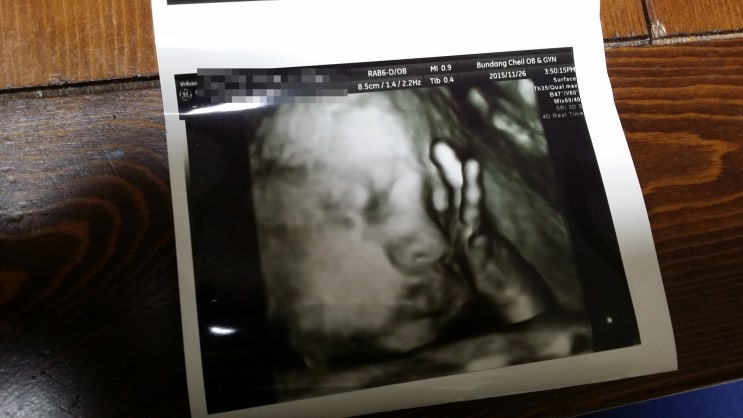

여덟번째만남. 임신 25주차/ 아홉번째만남.임신 28주차.3D입체초음파

2015.11.2 임신 25주차. 6개월 몸무게변화 한달전 +3.1키로 (50.8 ㅡ> 53.9) 임신시작부터는 +8.3키로 ...